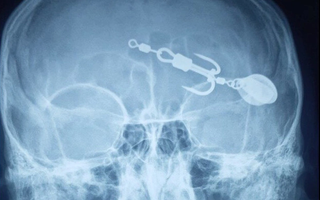

Lưỡi câu sau khi được lấy ra ngoài. Ảnh: BVCC

Sau khi các bác sĩ thăm khám và làm xét nghiệm cận lâm sàng, bệnh nhi được chẩn đoán dị vật hốc mắt trái và chỉ định phẫu thuật lấy dị vật hốc mắt. Sau phẫu thuật, sức khỏe của bệnh nhi ổn định, thị lực không bị ảnh hưởng và đã được xuất viện.